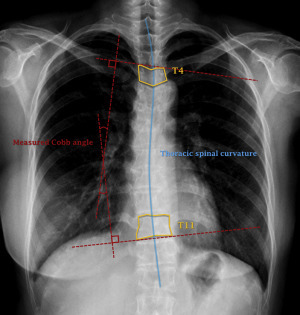

3. 유방 재건을 하면 자세가 한쪽으로 기울지 않아 척추가 덜 휜다.

한쪽의 가슴이 없어지게 되면 결국 한쪽으로 무게중심이 쏟아지게 되어, 이를 보상하기 위해서 척추에 어쩔 수 없는 무리가 간다. 이때 특이한 점은 유방절제를 시행한 쪽의 무게가 가벼워서 그쪽의 어깨가 올라가고 무거운 쪽이 내려가는 방향으로 척추가 휠 것 같지만, 오히려 반대로 유방이 남아있는 쪽을 자기도 모르게 힘을 주고 올리고 있게 되므로 절제 수술을 한 반대쪽으로 어깨가 치켜 올라가고 척추측만 또한 이러한 방향으로 진행되게 된다는 연구 보고가 있으며, 실제로도 한쪽 유방이 절제된 채로 오래 사신 분들 중 상당히 많은 분들이 등과 허리, 어깨의 통증을 호소하는 것을 자주 보게 된다.

그림4.jpg 한쪽의 가슴이 없어진 채로 오래 살게 되면, 어쩔 수 없이 신체의 자세가 영향을 받게 되고, 이에 따른 여러 가지 척추의 비대칭과 측만이 유발된다.

이와 반면에, 동시 유방 재건을 시행한 경우 재건을 하지 않은 환자들에 비하여 유의하게 등과 허리의 통증 유병률이 낮았으며, 척추의 휨 정도가 덜했고, 측만증의 유병률 또한 당연히 낮았다. 이는 유방 재건을 시행한 환자들의 가슴이 단순히 반대편 정상 측과 무게가 비슷하기 때문이었을 수도 있고, 혹은 재건을 한 환자들이 좀 더 열심히 재활치료에 참여하고 운동 또한 열심히 한 것이 원인일 수도 있지만, 결과론적으로 보았을 때 재건을 시행한 환자들에서 어깨 운동기능과 더불어 전체적인 신체 자세 (body posture)가 더 바르고, 근골격 계통의 무리가 덜 했음을 보여주는 결과이다.

역시 필자가 진행하고 작성한 논문. 한쪽의 유방암으로 인해 절제술을 시행한 환자들 중 재건을 시행한 환자들에서 척추의 휨 정도가 덜했고, 등과 허리 통증 유병률이 더 낮았다.